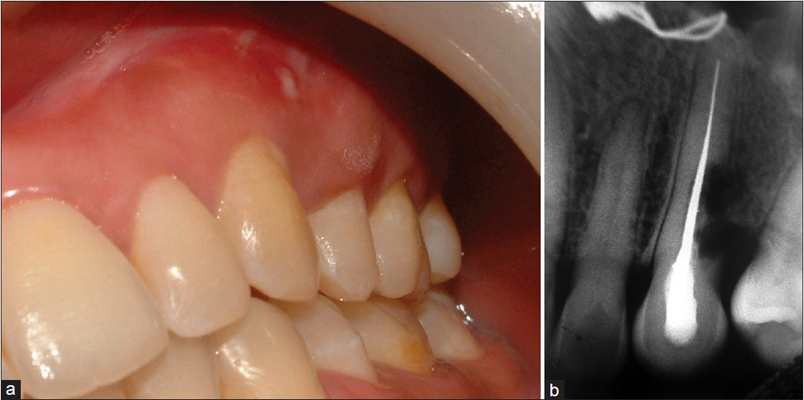

牙齦炎圖片

牙齦炎和牙周炎